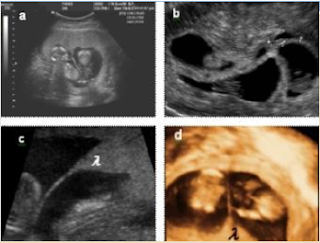

phân loại song thai:

- Chẩn đoán: sớm bằng SA đường âm đạo

- Thai 5 tuần: song thai 2 noãn với 2 túi thai riêng biệt, siêu âm có thể thấy rõ 2

túi thai.

- Thai 6 tuần: có thể thấy song thai 1 noãn với sự xuất hiện của 2 túi noãn hoàng

riêng.

- Thai 7 tuần: thấy rõ 2 phôi riêng với hai hình ảnh hoạt động của tim thai.

- từ 8 - 14 tuần: siêu âm đường bụng chẩn đoán loại phôi và loại rau thai

- siêu âm thấy 2 túi thai riêng, 2 bánh rau riêng thì đó là song thai 2 buồng ối, 2 bánh rau

hay song thai 2 noãn.

- Trên siêu âm chúng ta nhìn thấy 1 bánh rau, 2 buồng ối và thấy dấu hiệu Lambda (có

nghĩa là chỗ tiếp giáp giữa 2 buồng

ối có hình ảnh giống chữ Lambda (l

) trong tiếng Hy Lạp) thì ta chẩn đoán

là song thai 2 buồng ối, 1 bánh rau nhưng là song thai 2 noãn (vì 2 bánh rau nằm sát nhau).

Dấu hiệu Lambda

- Trên siêu âm chúng ta nhìn thấy 1 bánh rau, 2 buồng ối mà vách ngăn 2 buồng ối mỏng, không thấy dấu hiệu Lambda. Đó là song

thai 1 bánh rau, 2 buồng ối và là

song thai 1 noãn.

- Trên siêu âm thấy có 1 bánh rau, 1 buồng ối và 2 phôi riêng gọi là song thai 1 bánh

rau, 1 buồng ối và là song thai 1

noãn.

- Ngoài ra siêu âm cũng có thể thấy 2 giới tính khác nhau và trong trường hợp đó là

song thai 2 noãn.

Dấu hiệu chữ T